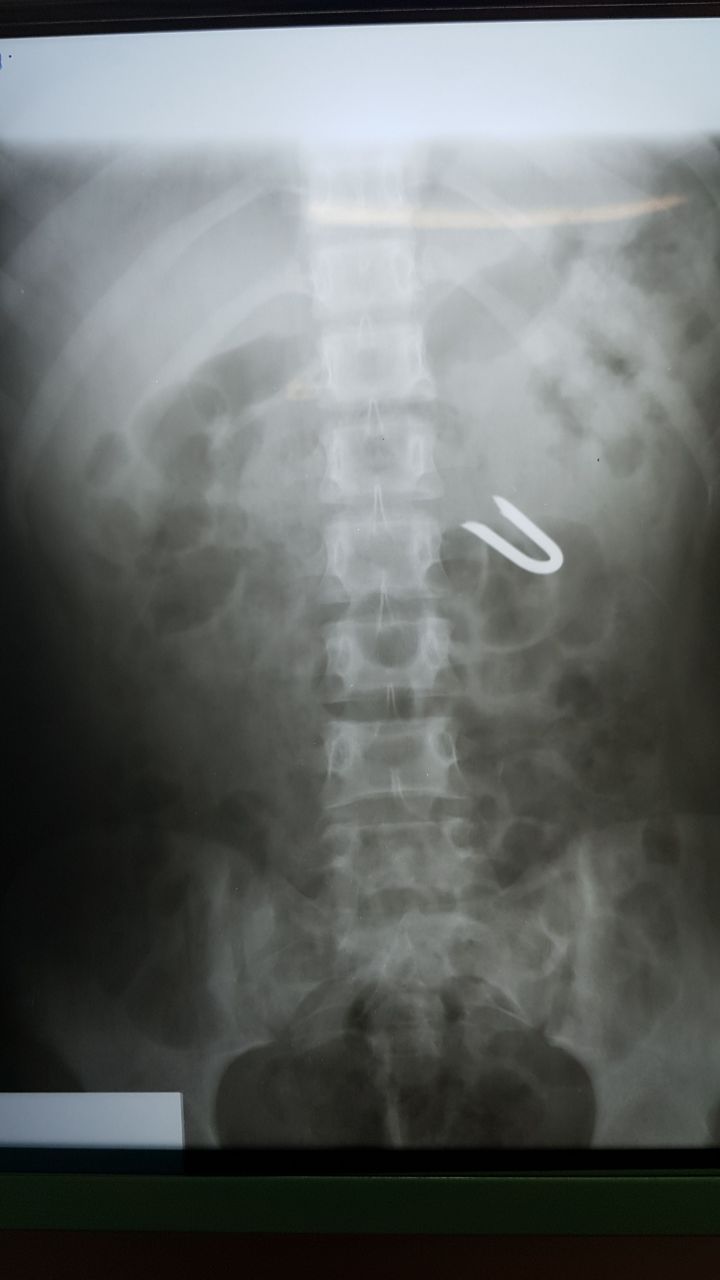

Patologías Quirúrgicas